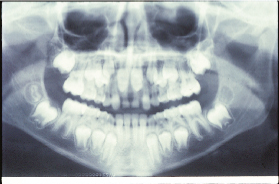

Hình 6: Rối loạn mọc răng của răng cửa giữa hàm trên liên quan đến răng dư tuberculate được minh họa ở hình 5 |

Sự hiện diện răng dư là nguyên nhân phổ biến nhất gây không mọc được răng cửa giữa hàm trên. Nó cũng có thể là nguyên nhân chậm thay răng sữa. Vấn đề thường được chú ý với việc mọc răng cửa bên hàm trên cùng với tình trạng không mọc được một hoặc cả hai răng cửa trung tâm (Hình 5 và 6). Răng dư ở các vị trí khác cũng có thể gây không mọc được các răng lân cận.

Sự chiếm chỗ